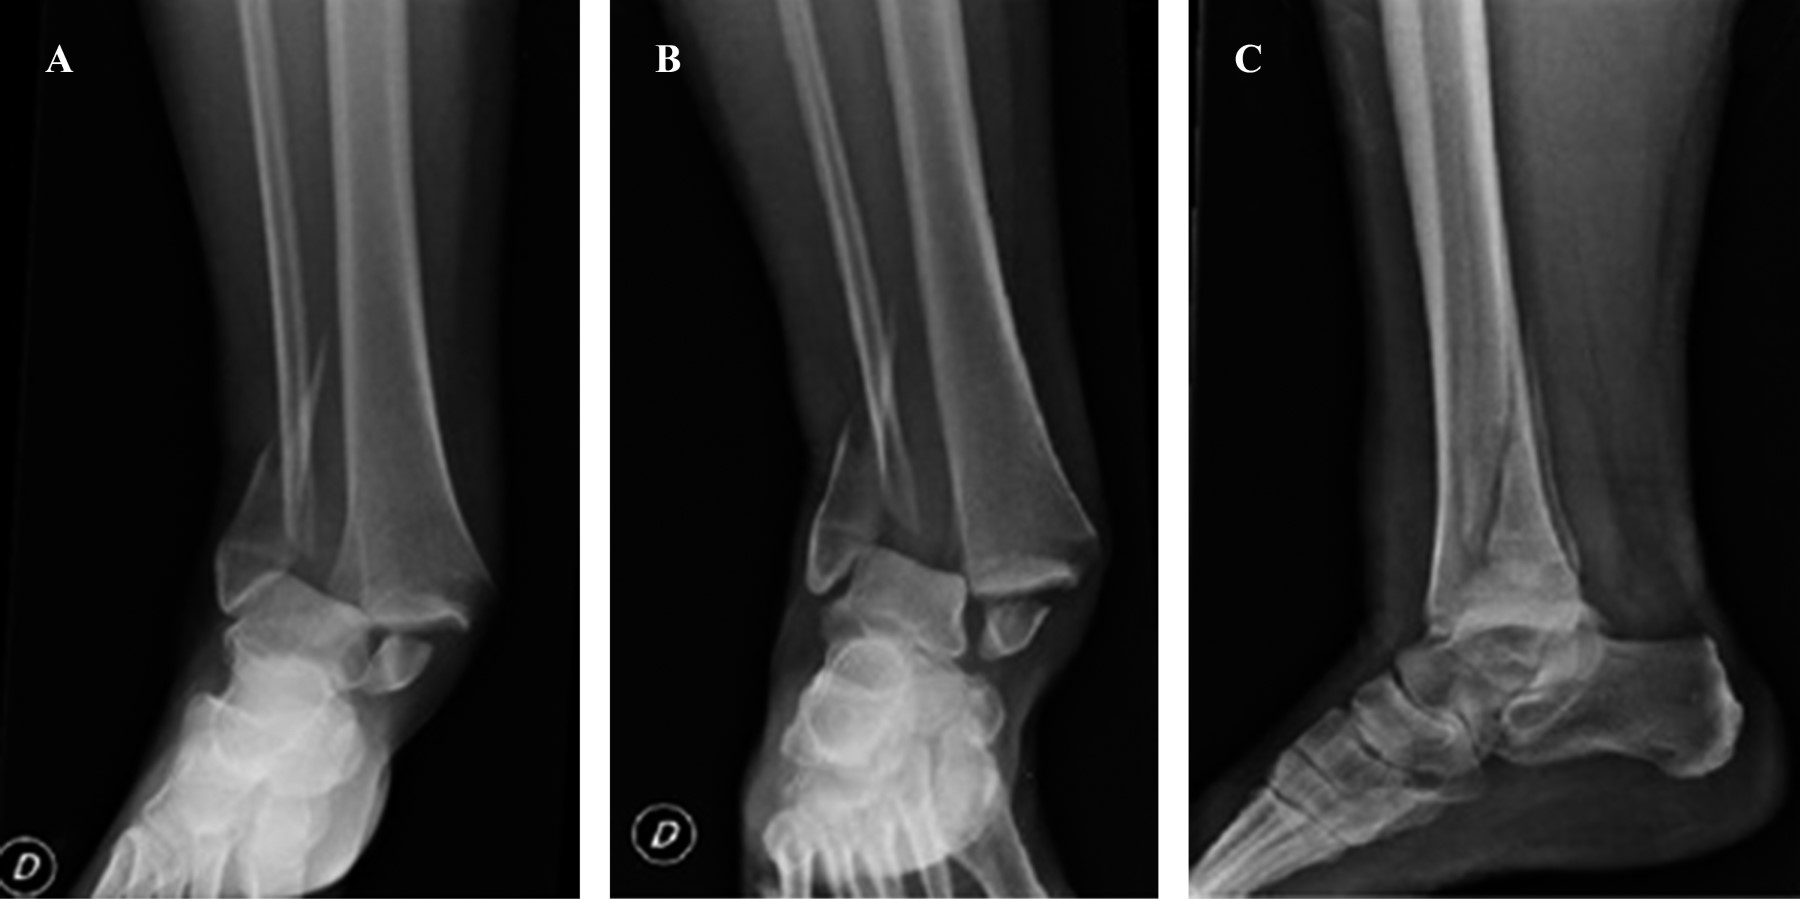

Al examen físico presenta impotencia funcional de tobillo derecho que impide la marcha. Se observa deformidad ósea e importante edema de partes blandas. Buen relleno capilar, pulsos periféricos positivos, movilidad limitada y sensibilidad con parestesias. Se decide realizar estudio radiográfico de tobillo derecho evidenciándose luxofractura del mismo (Figura 1), que correspondería a una 44-B3 dentro de la clasificación AO. A continuación, se procede a la reducción cerrada, inmovilización con valva corta de yeso en miembro inferior y posterior radiografía de control de la reducción (Figura 2). Se decide tratamiento quirúrgico programado cuatro días después, por lo que se indica tratamiento anticoagulante con enoxaparina 40 mg y suspensión del mismo un día previo a la cirugía.

Figura 1